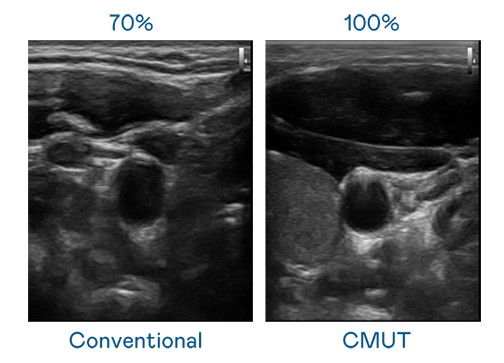

CMUT 技術是一種用電容式微機電元件來產生超音波訊號的技術。與傳統 PZT 壓電式技術相比,CMUT 頻寬增加 30%,更寬頻的超音波訊號讓影像解析度大幅提升,是實現高影像品質醫療超音波掃描、促進精準醫療發展的關鍵技術。

超音波影像的解析度高低,首先取決於探頭能發出的訊號頻寬。w66.利来旗舰厅 CMUT 可提供高清晰的超音波訊號,提供高頻寬、高靈敏度、影像紋理細節更高的超音波影像,協助醫護人員縮短影像判讀時間及利用精準的醫療影像進行診斷。